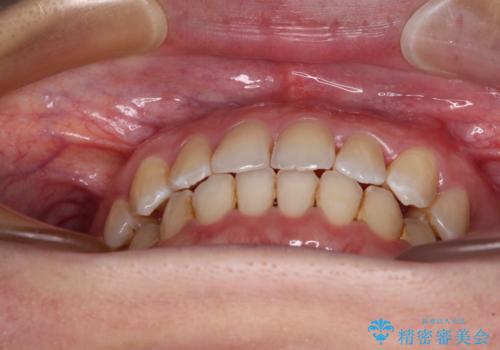

上顎の拡大に伴い反対咬合があっという間に改善されました。

元々の歯列不整は軽微であったため、僅か1年の期間で治療を終えることができました。